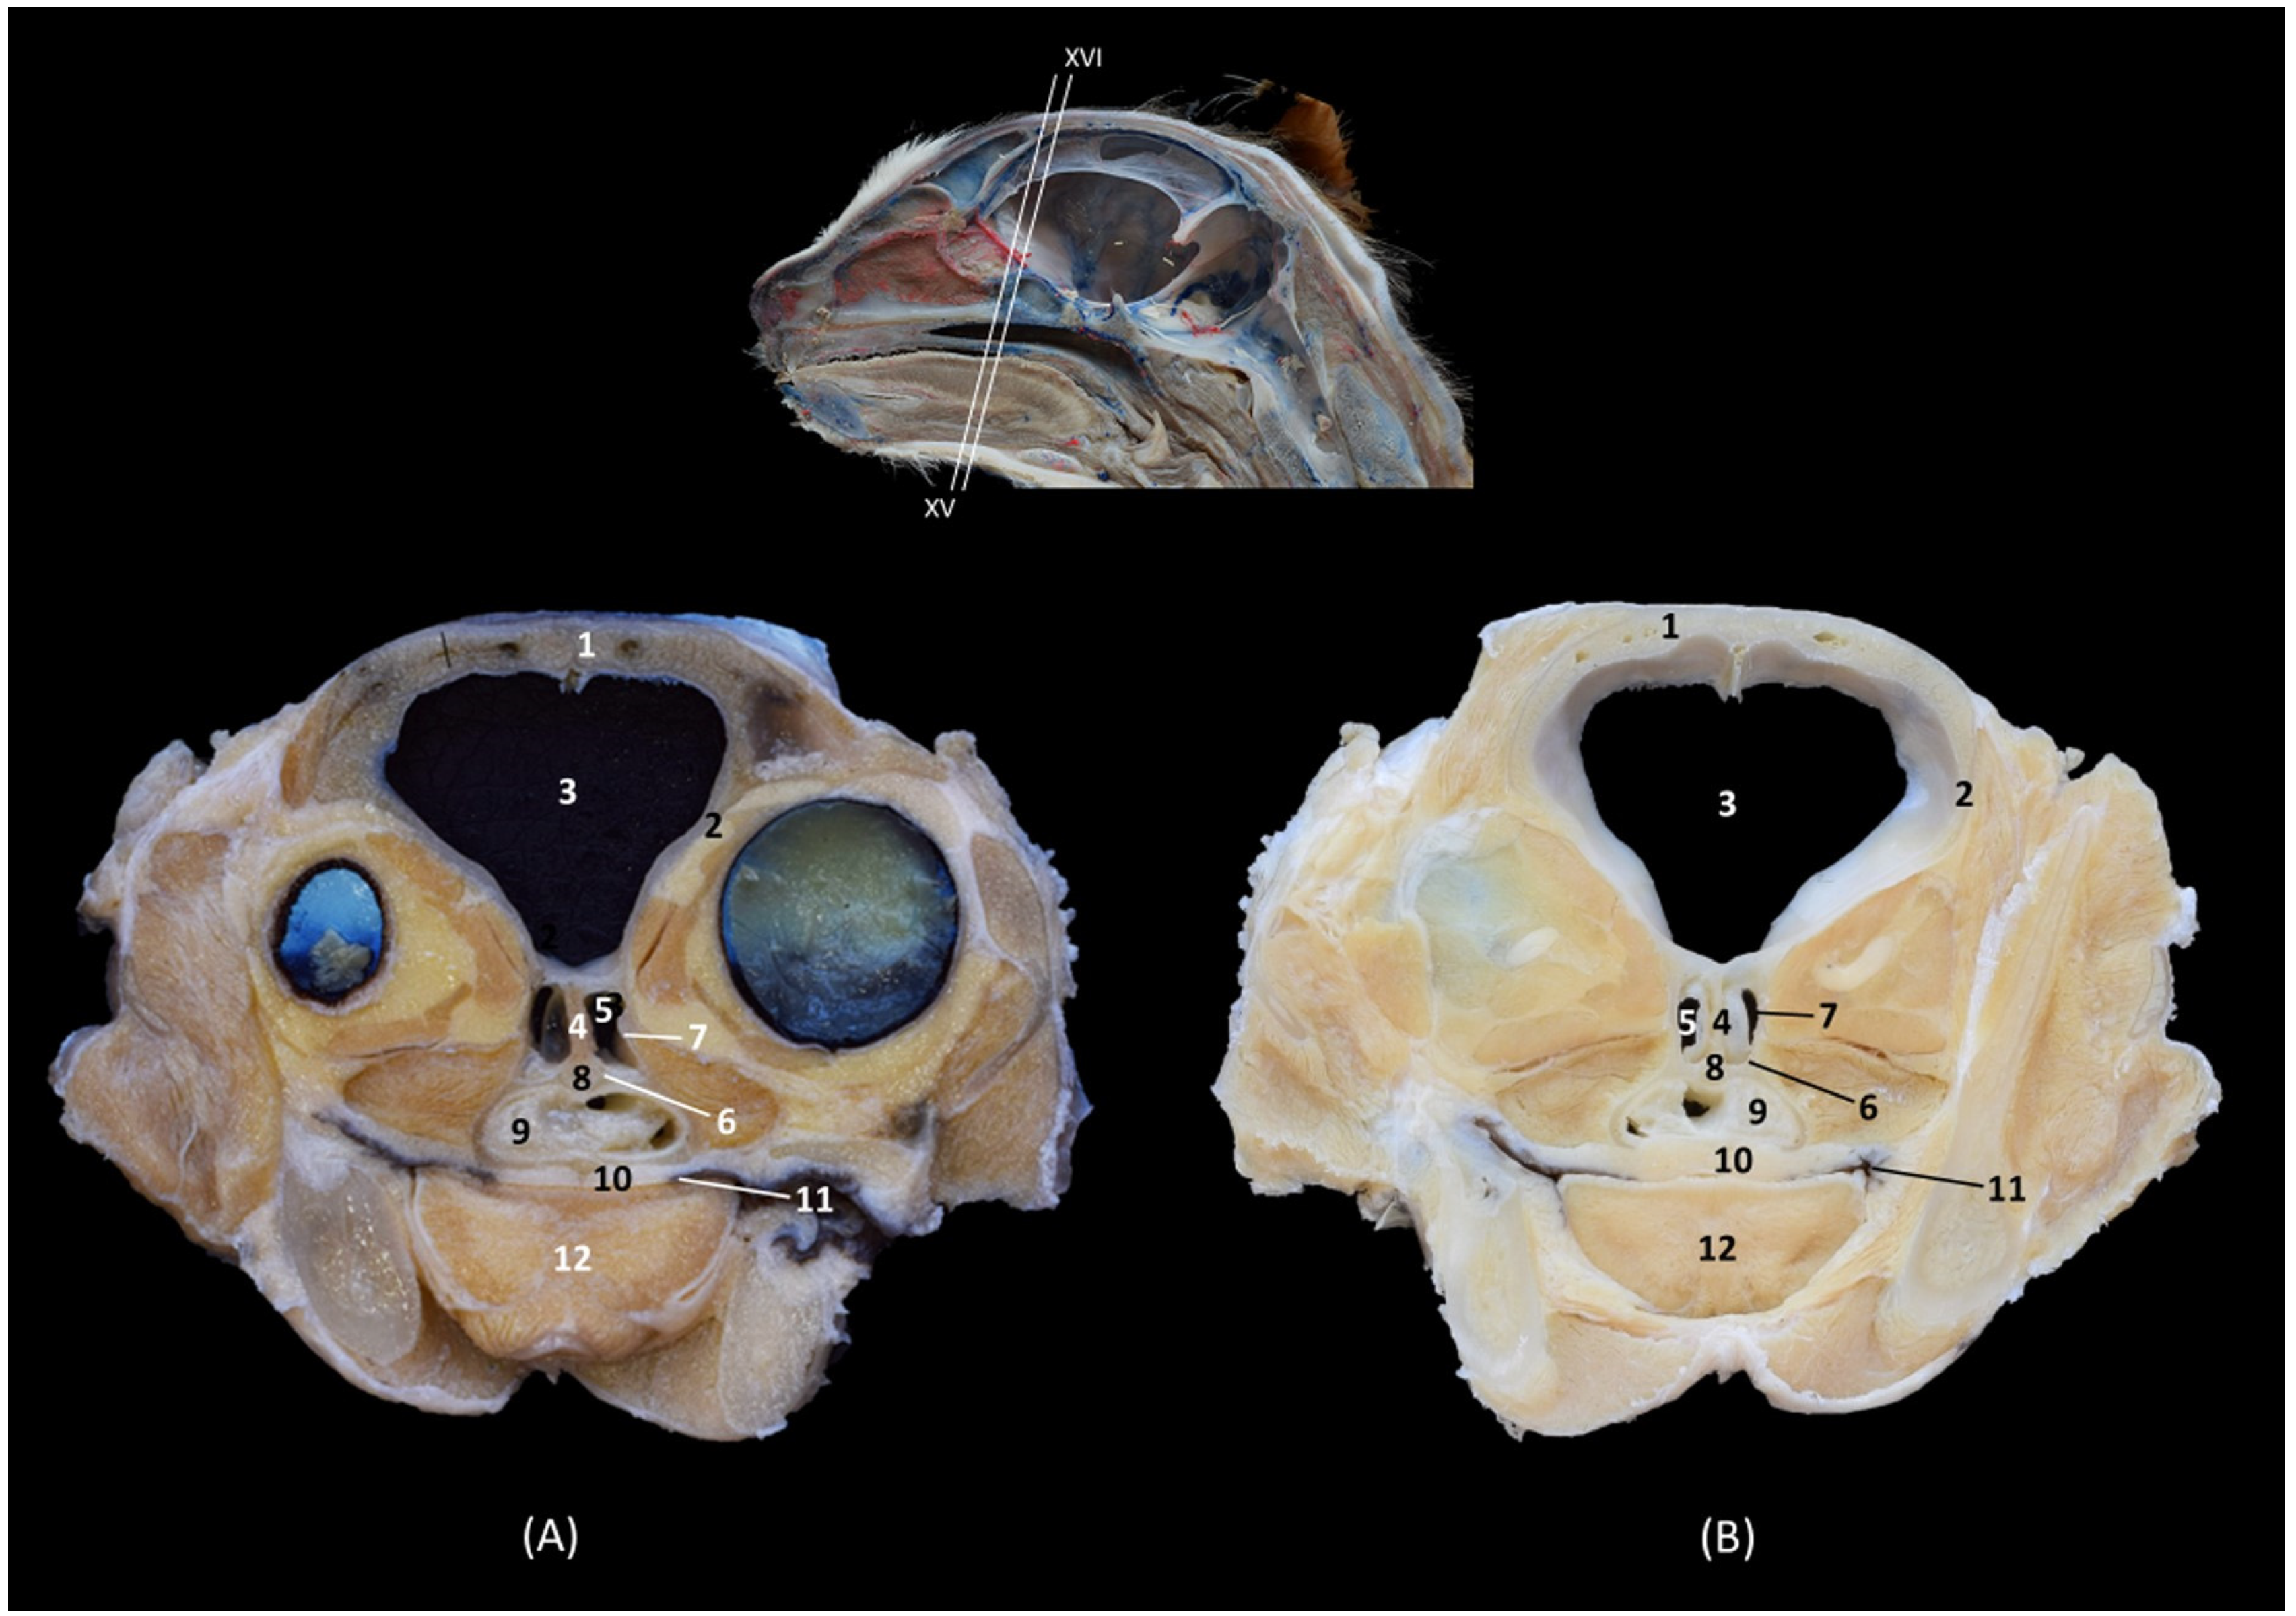

In this last transverse section (Figure 11), we observed dorsal to the nasopharynx (pars nasalis pharyngis) the caudal extension of the sphenoidal sinus.

Figure 11. Transverse anatomical sections of the cat’s head at the level of the paranasal sinuses and nasopharynx (pars nasalis pharyngis). (A): Rostral view, level section XV. (B): Caudal view, level section XVI. 1. Frontal bone; 2. Frontal bone: orbital surface; 3. Cranial cavity; 4. Sphenoidal sinus: septum; 5. Sphenoidal sinus; 6. Presphenoid bone: body; 7. Presphenoid bone: wing; 8. Vomer; 9. Nasopharynx (pars nasalis pharyngis): mucosa; 10. Soft palate; 11. Oropharynx; 12. Tongue.